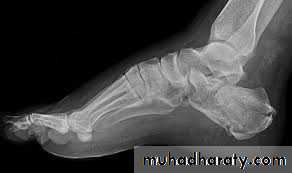

Calcaneal fracture, also known Don Juan fracture, is a fracture of the calcaneus. It is usually caused by a fall from height when one lands on their feet. These fractures represent approximately 2% of all fractures but 60% of tarsal bone fractures.